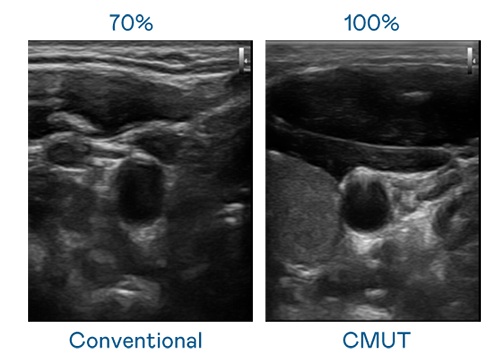

CMUT 技术是一种用电容式微机电元件来产生超音波讯号的技术。与传统 PZT 压电式技术相比,CMUT 频宽增加 30%,更宽频的超音波讯号让影像解析度大幅提升,是实现高影像品质医疗超音波扫描、促进精准医疗发展的关键技术。

大频宽带来超清晰影像

超音波影像的解析度高低,首先取决于探头能发出的讯号频宽。yy易游 CMUT 可提供高清晰的超音波讯号,提供高频宽、高灵敏度、影像纹理细节更高的超音波影像,协助医护人员缩短影像判读时间及利用精准的医疗影像进行诊断。